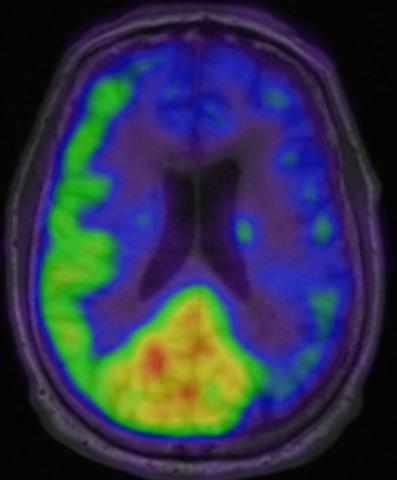

Den mest valide metode til påvisning af cerebral hypoperfusion og CVR er en 15O-H2O-PET [14], hvor der foretages en baselineskanning i hvile og en skanning 20 minutter efter infusion med acetazolamid eller under inhalation af CO2, som medfører dilatation af de cerebrale kar, og dermed gør det muligt at bestemme hjernens perfusion ved induceret hyperæmi. Ved at sammenligne hvileskanningen med skanningen, der blev foretaget efter indgift af acetazolamid eller CO2 fås et mål for CVR. En lav eller endda negativ CVR (såkaldt steal) indikerer, at den vaskulære reserve er opbrugt [16], hvilket betegnes som hæmodynamisk svigt og øger risikoen for apopleksi pga. nedsat blodgennemstrømning fokalt i hjernen i forsyningsområdet for det afficerede kar.

15O-H2O-PET/MR-skanning viser nedsat perfusion i venstre hemisfære efter indgift af acetazolamid.

LS-TIA er et symptom på transitorisk cerebral iskæmi og er forbundet med dårlig prognose med øget risiko for ny iskæmisk apopleksi og lavt funktionsniveau. Ved manglende kendskab til symptomet overses eller mistolkes det let. Da der er tale om et symptom, som kræver yderligere udredning, stiller det ekstra krav til opmærksomhed ved anamneseoptagelse og kliniske observationer. Tilstanden skyldes cerebral hypoperfusion på grund af storkarssygdom, hvilket sjældent ses på CT eller MR-skanning uden angiografi eller perfusionssekvenser. CT-angiografi vil oftest være førstevalg, da man med den med sikkerhed kan både afvise og påvise svær storkarssygdom. I det akutte forløb sikres det, at den cerebrale perfusion optimeres ved normohydrering, lejring og evt. pausering af antihypertensiv medicin. Udredningen og behandlingen er kompleks og vil ofte foregå i et multidiciplinært samarbejde imellem flere specialiserede afdelinger, som alle bør have specifik erfaring med cerebral hypoperfusion. Patienter, som har relevant storkarspatologi, og hvor man har mistanke om LS-TIA bør derfor henvises til neurologiske afdelinger med neurovaskulær kompentence med henblik på videre udredning og forløb. I Danmark er ekspertisen samlet på Aarhus Universitetshosptial og Bispebjerg Hospital/Rigshospitalet. Forløbet vil ofte inkludere en 15O-H2O-PET og en efterfølgende løbende vurdering af den medicinske behandling og stillingtagen til kirurgisk intervention.